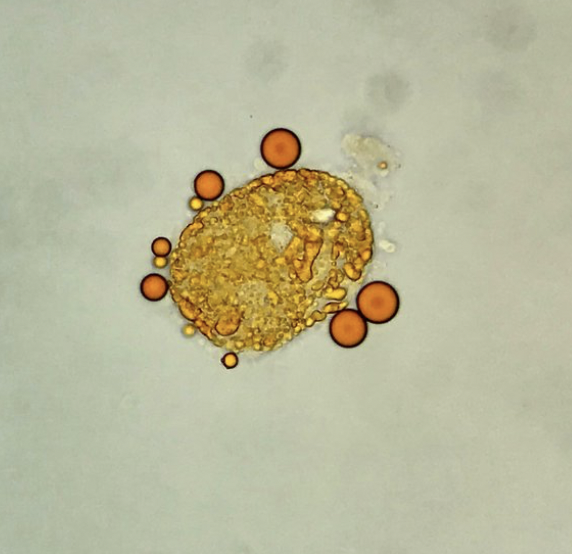

Sudan III is a lipophilic stain useful for the identification of lipids (neutral fats and triglycerides) in the urine, as an adjunct to polarization, or when polarized microscopy is not available. After usual sediment preparation add 3-5 drops of Sudan III and mix gently. Allow 15 minutes for stain uptake, then place a drop of this mixture on a slide with a cover glass. Lipid droplets (either as free droplets or incorporated in oval fat bodies or casts) appear yellow to orange/red.

Oval fat body and free lipid droplets – Sudan III stain